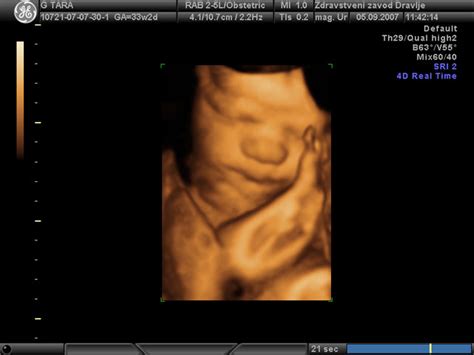

Rast ploda v nosečnosti

Velikost posteljice, njena rast in delovanje močno vplivajo na zdravje ploda in matere. Majhna posteljica lahko vodi do zastoja plodove rasti, medtem ko je velika posteljica pogosto povezana z zdravstvenimi težavami matere. Placentarna insuficienca nastane, ko posteljica ne deluje pravilno. Redni pregledi pri ginekologu so ključni za spremljanje rasti in razvoja posteljice ter ploda.

V nosečnosti se rast ploda spremlja z meritvami, kot so obseg glavice (HC), obseg trebuha (AC) in dolžina stegnenice (FL). Te meritve se primerjajo s percentili, ki kažejo, kje se plod nahaja glede na pričakovane vrednosti za določeno gestacijsko starost. Odstopanja od pričakovanih vrednosti zahtevajo natančnejše spremljanje in po potrebi dodatne preiskave, kot je test za nosečniško sladkorno bolezen (OGTT).

Nosečnost traja približno 40 tednov. Porod donošenega otroka pričakujemo med dopolnjenim 37. in 42. tednom. Vsaka faza nosečnosti prinaša specifičen razvoj ploda, od prvih celic do popolne zrelosti za življenje zunaj maternice.